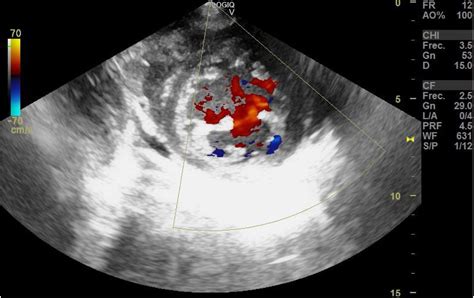

To better understand Non Compaction Cardiomyopathy, it is helpful to visualize the heart's anatomy. Typically, the heart walls are smooth and dense. In patients with NCCM, the myocardium (the heart muscle) remains thin and features excessive trabeculations—small, finger-like projections—and deep inter-trabecular recesses. These structural flaws create a "spongy" appearance when viewed through imaging techniques.

Diagnosing Non Compaction Cardiomyopathy primarily involves advanced cardiac imaging. Physicians utilize specific diagnostic criteria to differentiate NCCM from a normal heart that may just have prominent, yet healthy, trabeculations.

Echocardiogram The first-line imaging test to visualize structure and blood flow.